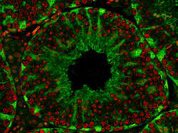

Новый нейростимулятор вживляют прямо в мозг

Управление по продуктам и лекарствам США (FDA) дало свое согласие на внедрение в медицинскую практику имплантируемого в мозг устройства RNS System (responsive neurostimulator), снижающего частоту приступов у людей, страдающих эпилепсией.